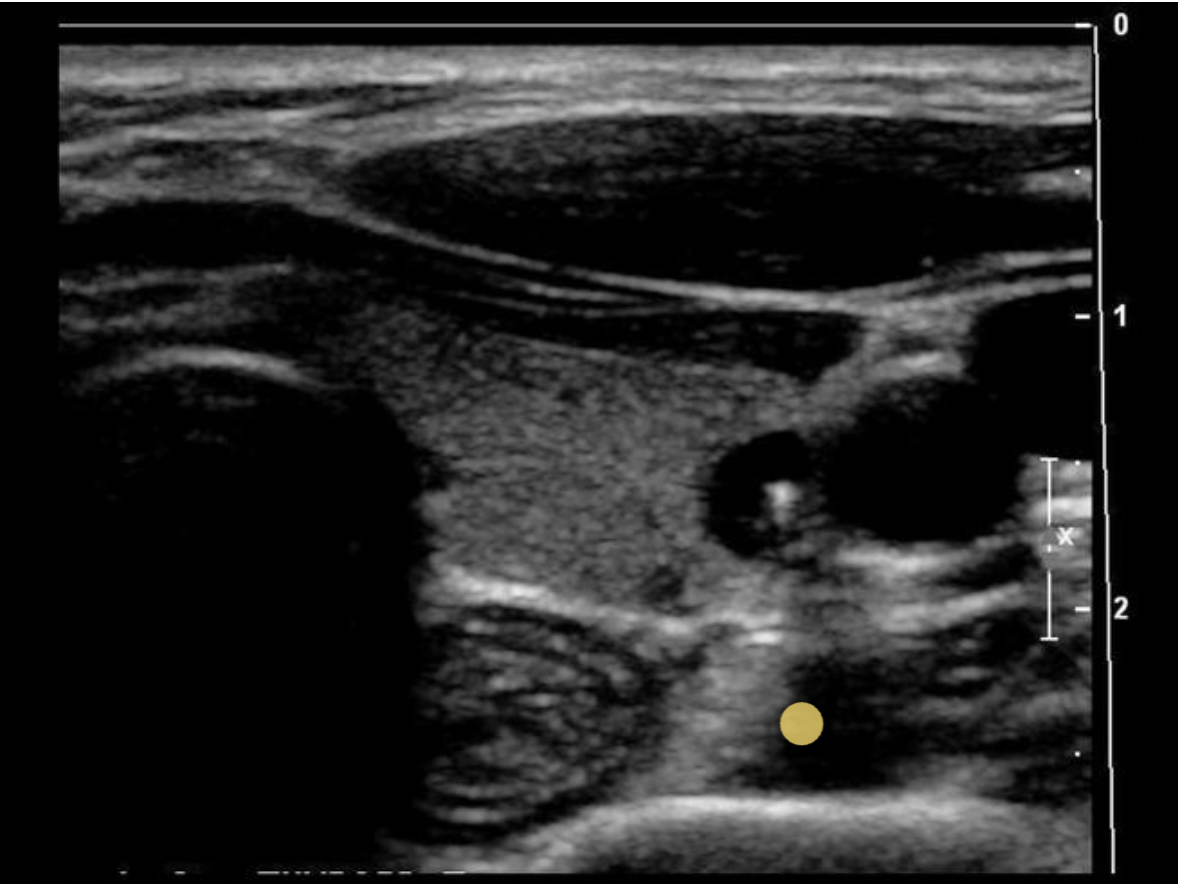

Which blood vessel is located lateral to the left lobe of the thyroid and demonstrates an anechoic ovoid shape in a transverse view of the mid thyroid?

B. left internal jugular vein

The internal jugular vein is located lateral to the left lobe of the thyroid and demonstrates an anechoic ovoid shape in a transverse view of the mid thyroid. The carotid artery is also lateral to the thyroid lobes but it should be a circular structure.

The image displays the left lobe of the thyroid with the circular CCA immediately lateral to the mid lobe and ovoid IJV lateral to the CCA.

Which blood vessel is located lateral to the right lobe of the thyroid and demonstrates an anechoic circular shape in a transverse view of the mid thyroid?

C. right common carotid artery

The right common carotid artery is located lateral to the right lobe of the thyroid and demonstrates an anechoic circular shape in a transverse view of the mid thyroid.

Find the internal jugular vein

The common carotid artery is lateral to the thyroid gland. The internal jugular vein is slightly anterior and lateral to the common carotid artery.